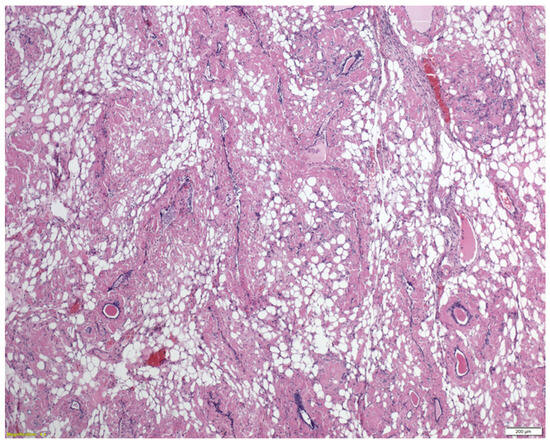

A Rare Case of Systemic Amyloidosis Involving the Thyroid in a Young Patient

by Oliwia Julia Kasprzak, Kamila Stępińska, Kaja Kiedrowska, Tomasz Błaszkowski, Aleksandra Kudrymska, Sylwia Sikora, Maciej Miernik and Maciej Romanowski

J. Clin. Med. 2025, 14(19), 6741; https://doi.org/10.3390/jcm14196741 - 24 Sep 2025

Thyroid amyloidosis is a rare condition associated with thyroid pathologies such as medullary carcinoma, papillary carcinoma, amyloid goitre, and benign lesions, with a clinically palpable goitre being exceptionally uncommon. As a result, many cases of benign thyroid enlargement caused by amyloid deposits remain [...] Read more.

Thyroid amyloidosis is a rare condition associated with thyroid pathologies such as medullary carcinoma, papillary carcinoma, amyloid goitre, and benign lesions, with a clinically palpable goitre being exceptionally uncommon. As a result, many cases of benign thyroid enlargement caused by amyloid deposits remain undiagnosed. A 28-year-old male patient noticed progressive neck circumference enlargement, voice alteration, decreased appetite, weight loss, dysphagia, fever, and night sweats. Fine-needle aspiration biopsy of the thyroid gland did not reveal the cause of the goitre. A total thyroidectomy was performed. Histopathological examination confirmed advanced thyroid amyloidosis. Full article

Show Figures

Figure 1